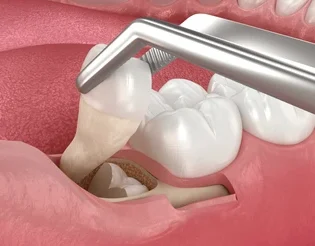

Wisdom Teeth Removal

Wisdom teeth are the last set of molars that usually appear between the ages of 17 and 25. In many cases, these teeth don’t have enough space to grow properly, leading to pain, infection, swelling, or misalignment of nearby teeth. At Rootssuperspecialitydental, we provide safe, gentle, and expert wisdom teeth removal to protect your oral health and prevent future dental issues.

Our experienced dentists perform the procedure with modern equipment and pain-free techniques, ensuring a comfortable and stress-free experience. Whether it’s a simple extraction or a surgical removal, we focus on precision, hygiene, and quick recovery.

Removing problematic wisdom teeth can relieve pain, prevent infection, and protect your other teeth from shifting or decay. We also provide personalized aftercare instructions to help you heal faster and stay comfortable.